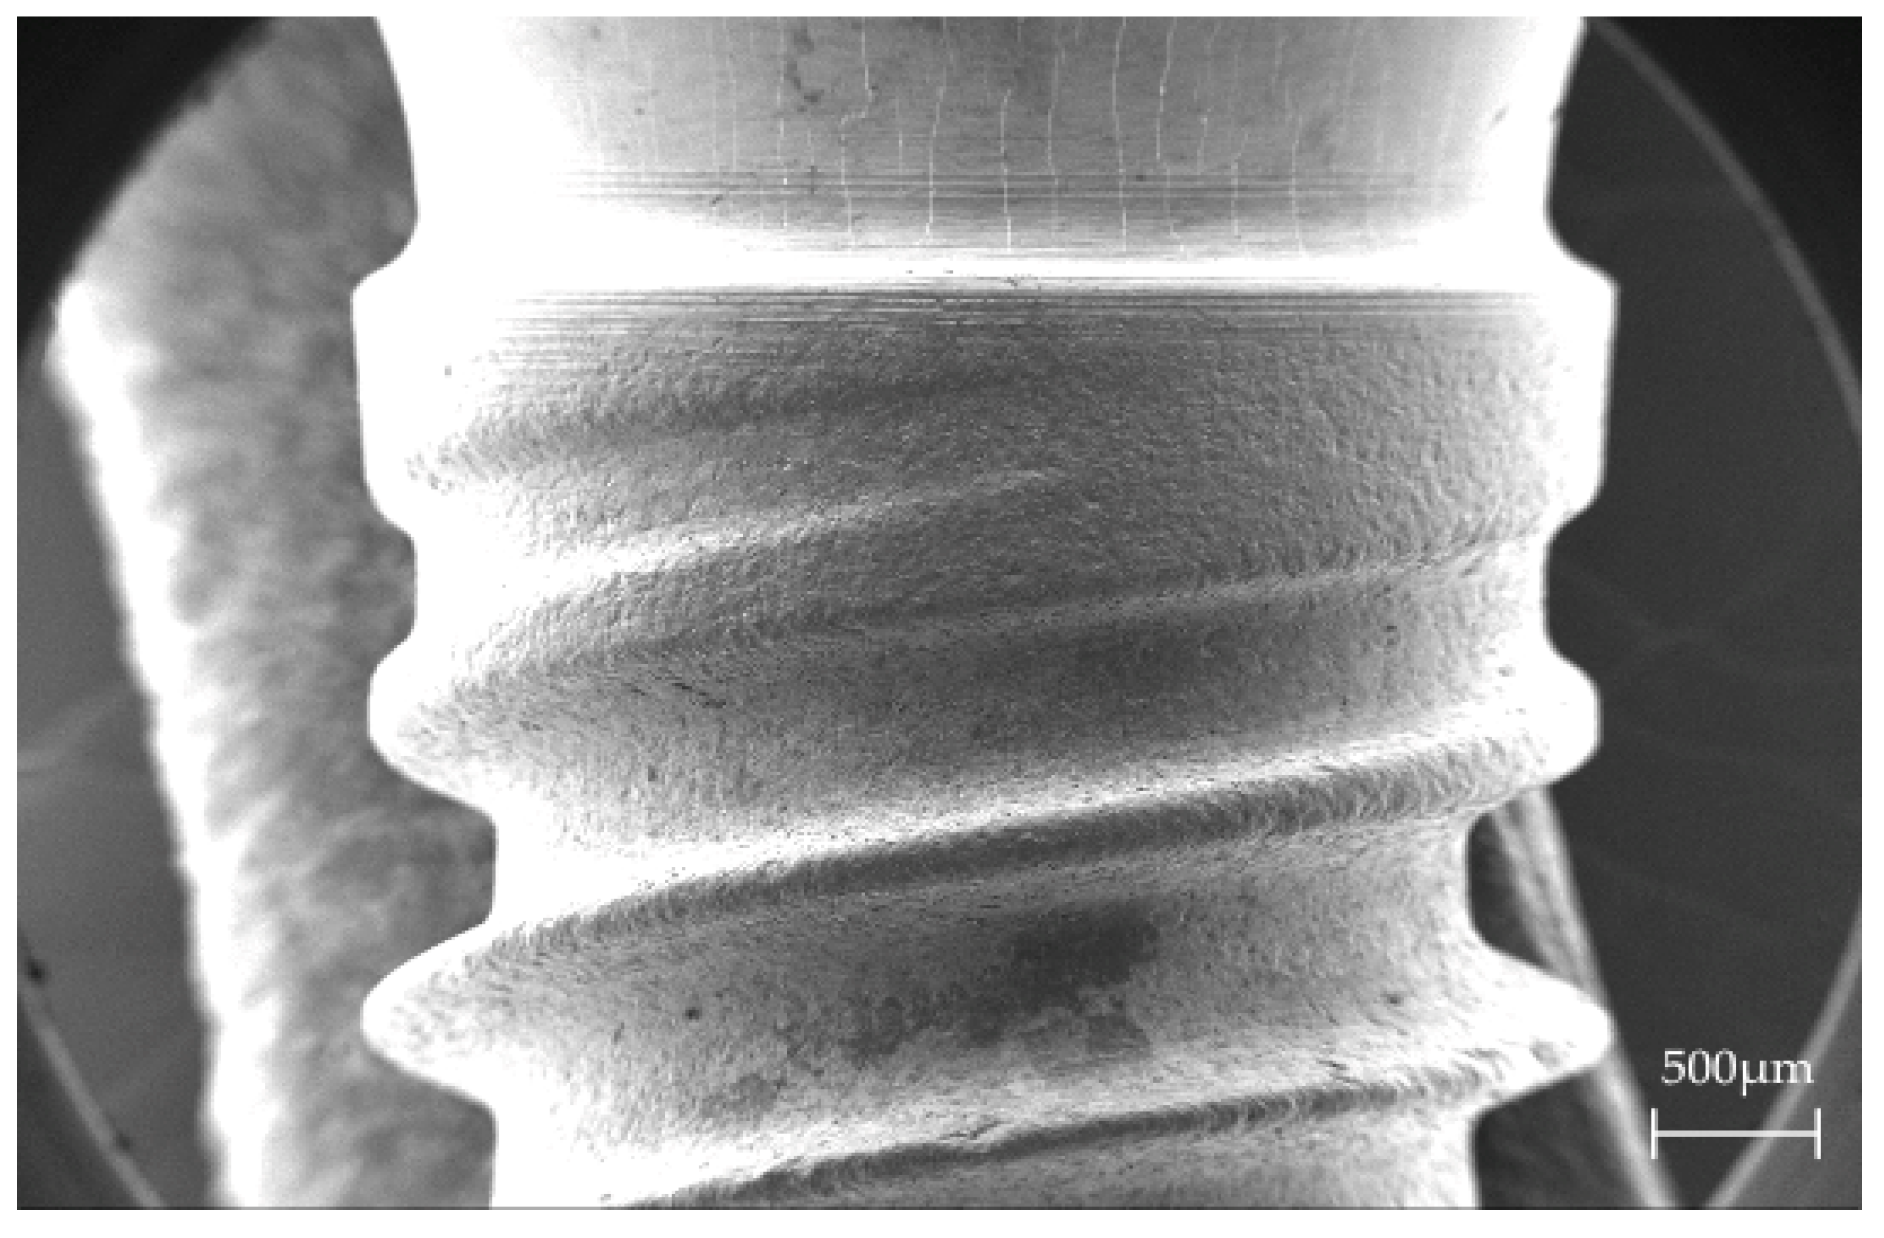

3.1. Scanning Electron Microscopy